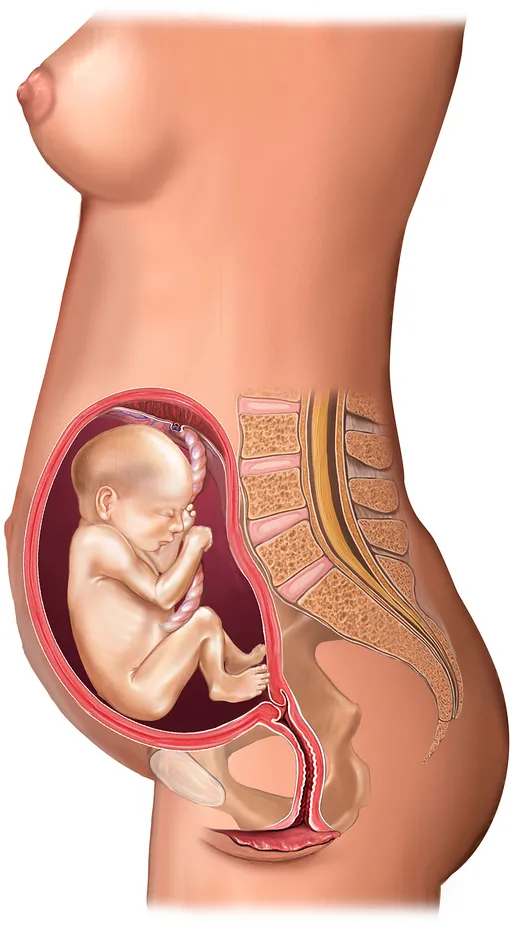

Расположение плода на 15-й неделе беременности: фотографии и иллюстрации